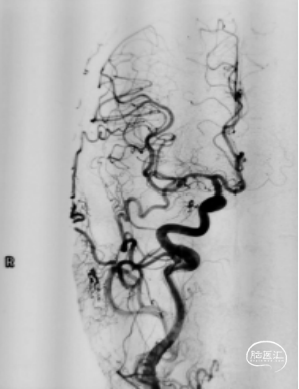

2024-03外院DSA

1. 右颈内动脉:(图1)

图1